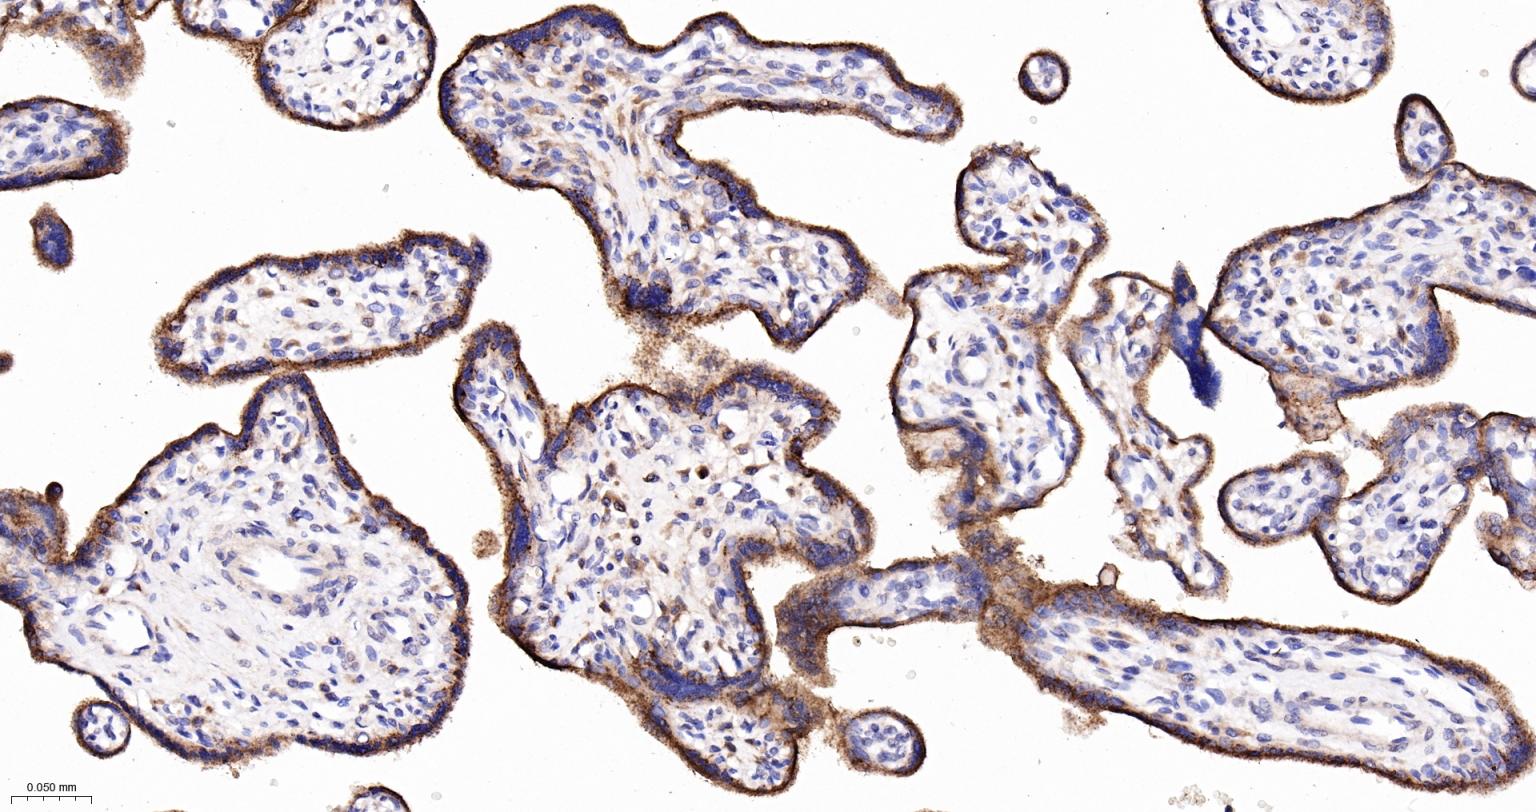

Paraformaldehyde-fixed, paraffin embedded Human placenta;Antigen retrieval by boiling in sodium citrate buffer (pH6.0) for 15 min; Antibody incubation with LAMP2 Monoclonal Antibody, Unconjugated (bsm-61207R) at 1:200 overnight at 4°C, followed by conjugation to the bs-0295G-HRP and DAB (C-0010) staining.